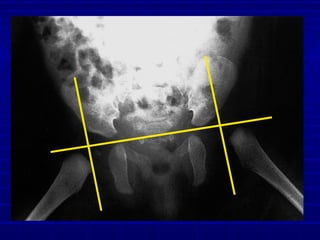

ImagingImaging

 RadiographsRadiographs

 Acetabular IndexAcetabular Index

< 30° wnl

RadiographsRadiographs

Newborns 27.5 degrees

6 months 23.5 degrees

2 years 20 degrees